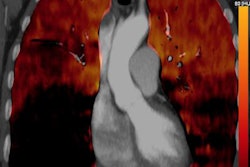

VIENNA - When you mention pulmonary embolism (PE), the chances are you will think of Dr. Martine Rémy-Jardin, PhD, professor of radiology and head of the department of cardiothoracic imaging at the University Centre of Lille in France. In this video interview, she speaks about persistent controversies in PE and how to optimize patient management.

Dr. Martine Rémy-Jardin, PhD, speaks about persistent controversies in pulmonary embolism and how to optimize patient management.